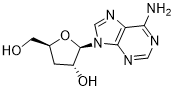

馬鞍山致研生物醫(yī)藥科技有限公司成立于馬鞍山市鄭浦港新區(qū)現(xiàn)代產(chǎn)業(yè)園。公司專(zhuān)注于生物小分子、醫(yī)藥中間體相關(guān)產(chǎn)品的研發(fā)和生產(chǎn),產(chǎn)品主要包括DNA亞磷酰胺單體、RNA亞磷酰胺單體、特殊單體以及按照客戶(hù)要求定制的RNA和DNA,并且公司提供定制合成等方面的研究服...

馬鞍山致研生物醫(yī)藥科技有限公司成立于馬鞍山市鄭浦港新區(qū)現(xiàn)代產(chǎn)業(yè)園。公司專(zhuān)注于生物小分子、醫(yī)藥中間體相關(guān)產(chǎn)品的研發(fā)和生產(chǎn),產(chǎn)品主要包括DNA亞磷酰胺單體、RNA亞磷酰胺單體、特殊單體以及按照客戶(hù)要求定制的RNA和DNA,并且公司提供定制合成等方面的研究服...